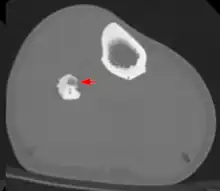

Les radiographies de l'ostéome ostéoïde montrent généralement une clarté ronde, contenant un nidus central sclérotique dense (la lésion caractéristique de ce type de tumeur) entouré d'os sclérotique. Le nidus est rarement plus grand que 1,5 cm.[réf. nécessaire]

La lésion peut dans la plupart des cas être détectée au scanner, à la scintigraphie osseuse et à l'angiographie.

L'IRM n'ajoute que peu aux résultats.

La tomodensitométrie est utile pour la localisation. Le balayage des radionucléides montre une absorption intense qui permet la localisation à l'aide d'un détecteur portatif lors d'une intervention chirurgicale et permet de confirmer que la totalité de la lésion a été retirée[3],[4].